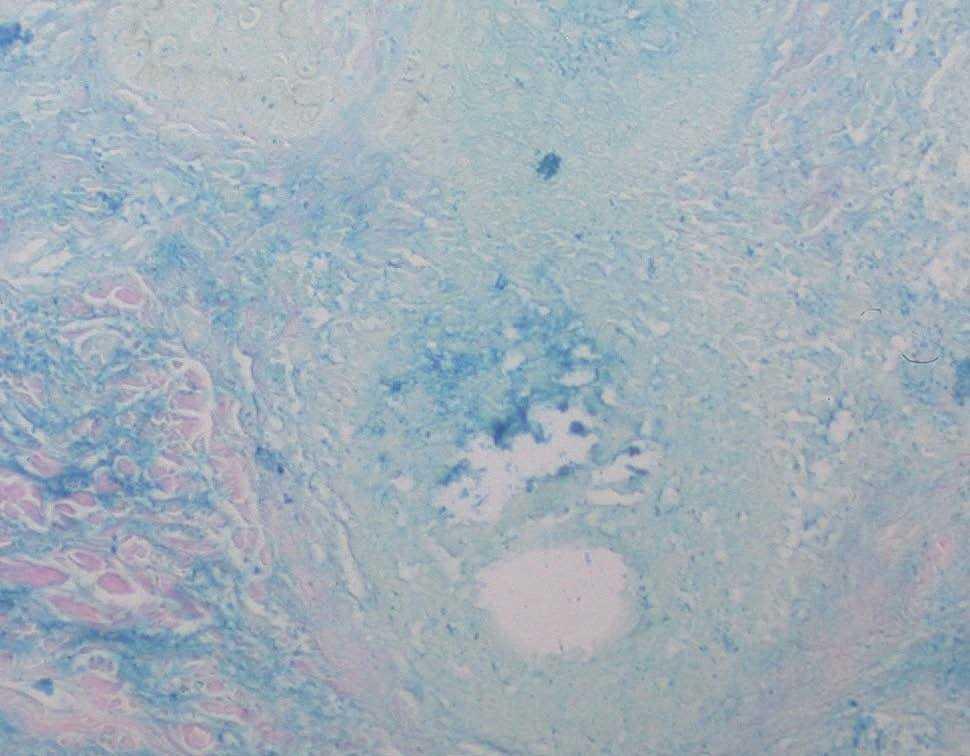

Se practicó una biopsia cutánea que mostró una epidermis normal sin alteraciones de la membrana basal. Destacaban infiltrados linfocitarios de predominio perifolicular y grandes espacios quísticos con pérdida de la conexión entre los queratinocitos foliculares (fig. 2). La tinción con hierro coloidal mostró depósitos de mucina en estos espacios quísticos (fig. 3). Se realizaron las siguientes exploraciones complementarias con resultados normales y/o negativos: inmunofluorescencia directa de piel afectada, recuento, fórmula y bioquímica sanguínea básicas, hormonas tiroideas, anticuerpos antinucleares, anti-ADN, anti-Ro y anti-La.

Fig. 3.—La tinción de hierro coloidal pone de manifiesto la existencia de gran cantidad de mucina ×100.